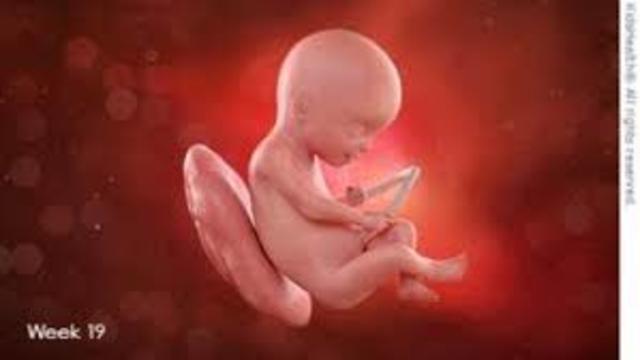

• semana 19 de embarazo

semana 19 de embarazo

A las 19 semanas de embarazo, el sistema nervioso del bebé, en especial el cerebro, se está desarrollando y creciendo rápidamente. El cartílago suave que forma el esqueleto del bebé se está endureciendo para convertirse en huesos. Por otro lado, el bebé ya hace movimientos activos que son más fáciles de sentir. Te darás cuenta de que hay momentos en los que el bebé parece estar dormido y otros en que se mueve mucho. Esto se debe a que duerme más y se despierta con más energía.